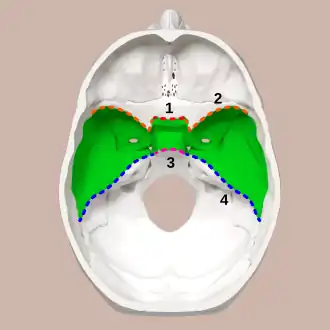

Superior view of the skull base. Middle cranial fossa shown in green. 1: Sphenoidal limbus (anterior margin of the chiasmatic groove) | |